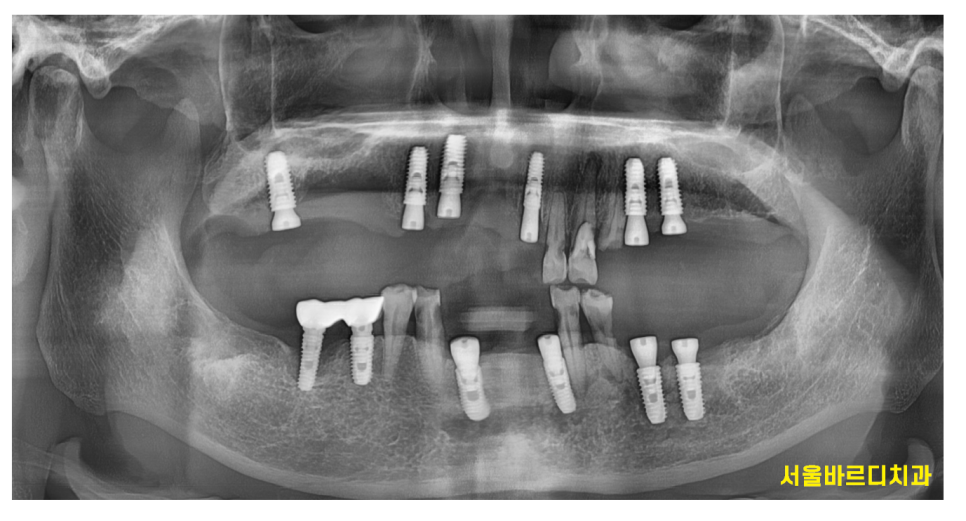

천호동 치과 치료의 끝나고 촬영한 X RAY입니다.

CT대로 분석하고 임플란트를 하다보니

처음 계획대로 치료가 완료되었습니다.

이제 위 아래 치아끼리 맞물리니

빠른 시기로 충치가 많이 먹은 치아들을 치료하는 것으로

2차 계획을 세워야겠습니다.